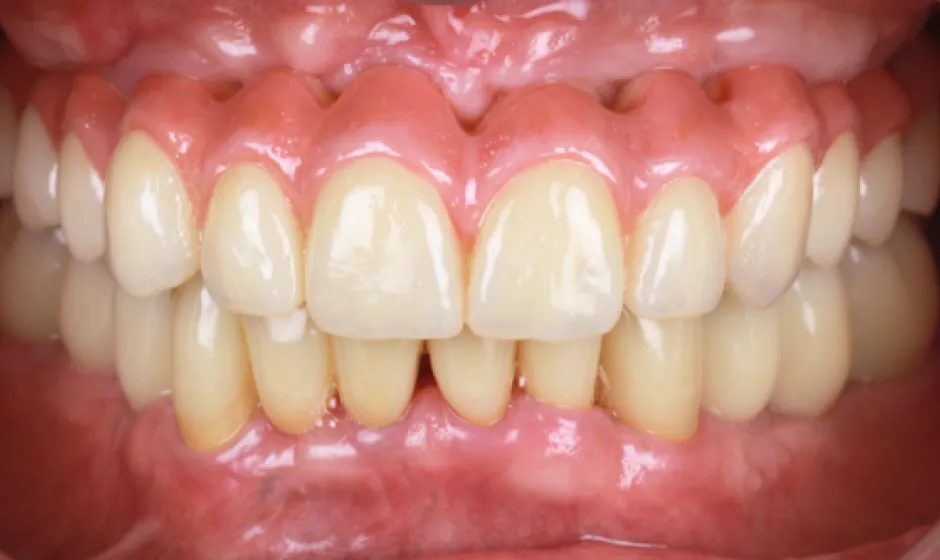

症例2

- 治療名

- 【高度審美形成】歯間乳頭再建術

- 患者様

- 40代女性

- 執刀医

- Dr. 大杉

- 治療期間

- 約1年

- 治療費

- 300,000円(税込)

- リスク

- 移植組織の定着後も、メンテナンスが予後を大きく左右します。

特に歯間ブラシの不適切な使用や過度なブラッシング圧は組織の退縮を招くため、術後は当院の指導に基づいた厳密なプラークコントロールが必要です。